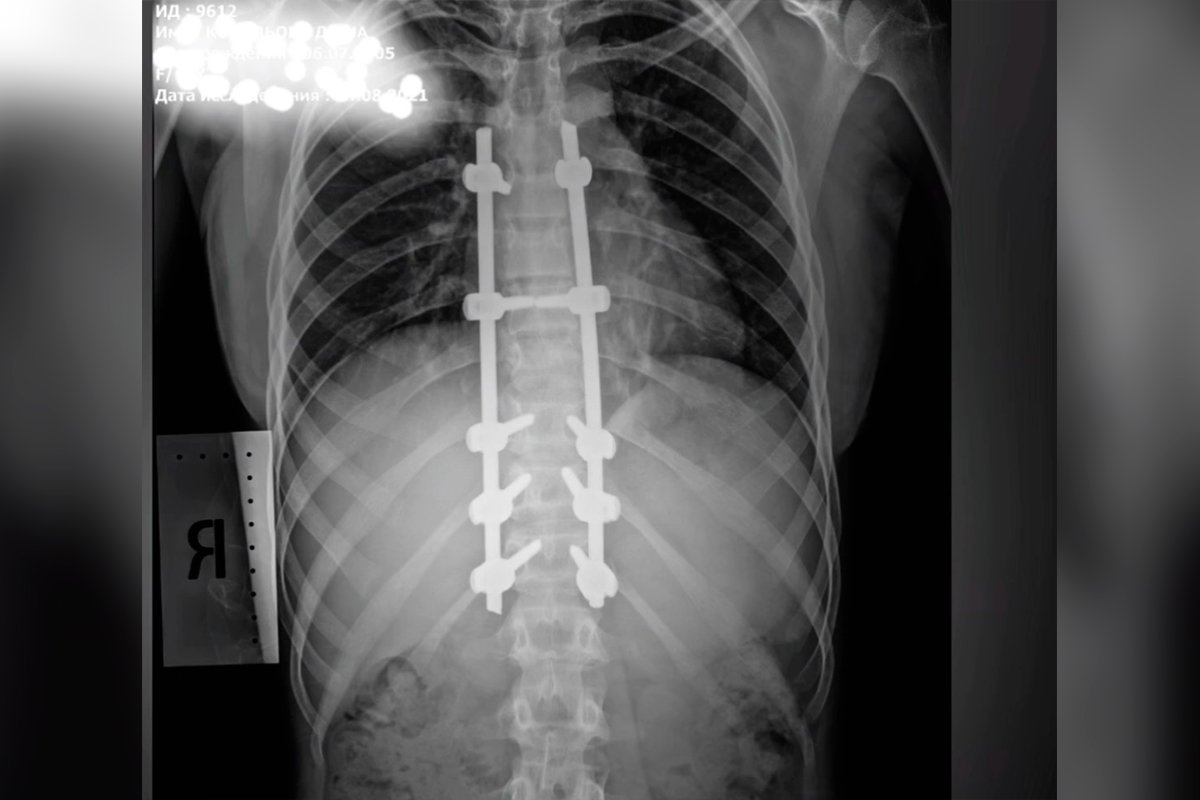

17 июля 16-летняя Дарья Ковалева выпала из окна третьего этажа детского лагеря «Днепр» в селе Счастливцево Херсонской области. По словам девочки, она залезла на перила, чтобы поймать телефонную связь, но не удержалась и упала, из-за чего получила множественные травмы, в том числе – компрессионный перелом трех грудных позвонков.

28 июля Дарье в Днепре провели операцию на позвоночнике. Сейчас она уже самостоятельно ходит, а 4 августа ее выписали из больницы. Девочка продолжает ежедневно ездить в медицинское учреждение на перевязки. Об этом Информатор сообщает со ссылкой на детское ортопедо-травматологическое отделение больницы Руднева. Вместе с врачами учреждения операцию проводила и целая команда специалистов, которые приехали в Днепр из Харькова.

«Операция длилась 3,5 часа. Уже в первые послеоперационные сутки девочка самостоятельно села в постели, а на вторые сутки - встала на ноги. Врачи разных медицинских учреждений и из разных городов Украины объединились в единую команду ради выздоровления ребенка. Дарья выздоравливает и уже выписана домой», - сообщили в больнице Руднева.